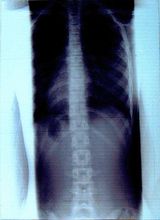

症例11)

体操3ヶ月で15度が計測不能となりました。これが大塚式体操の力

平成18年12月 玉川病院 整形外科受診8歳女子検診15度と診断。

平成19年 1月 大塚整体初診 体操4回指導。

平成19年 3月 再検診へ同病院へ。計測不能。

平成19年 3月 レントゲン持参され本日で終了、自宅体操の継続を指導。

平成18年12月

平成19年3月

15度

計測不能